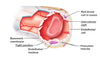

Layers of the heart

Epicardium description

Thin layer of flat to cuboidal mesothelial cells covering fibrous and adipose connective tissue (also called the visceral layer of the pericardium)

Epicardium contains

- nerves

- blood vessels

that supply the heart

Myocardium description

- the thickest layer of the heart

- composed of bundles of cardiac muscle cells organized into spiraling fascicles that efficiently squeeze blood out of the heart chambers

Endocardium description

Simple squamous epithelium over a layer of variable thickness connective tissue called the subendocardium